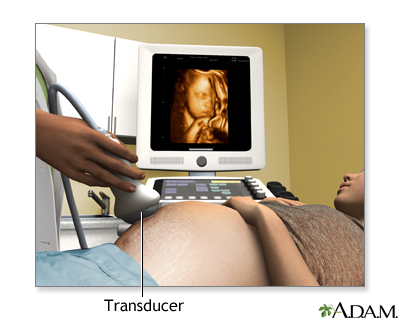

How the Test is Performed

To have the procedure:

- You will lie on your back on an exam table.

- The person performing the test will spread a clear, water-based gel on your belly and pelvis area. A handheld probe will then be moved over the area. The gel helps the probe transmit sound waves.

- These waves bounce off the body structures, including the developing baby, to create a picture on the ultrasound machine.

In some cases, a pregnancy ultrasound may be done by placing the probe into the vagina. This is more likely in early pregnancy. Many women will have the length of their cervix measured by vaginal ultrasonography around 20 to 24 weeks of pregnancy.

How the Test will Feel

There may be some discomfort from pressure on the full bladder. The conducting gel may feel slightly cold and wet. You will not feel the ultrasound waves.